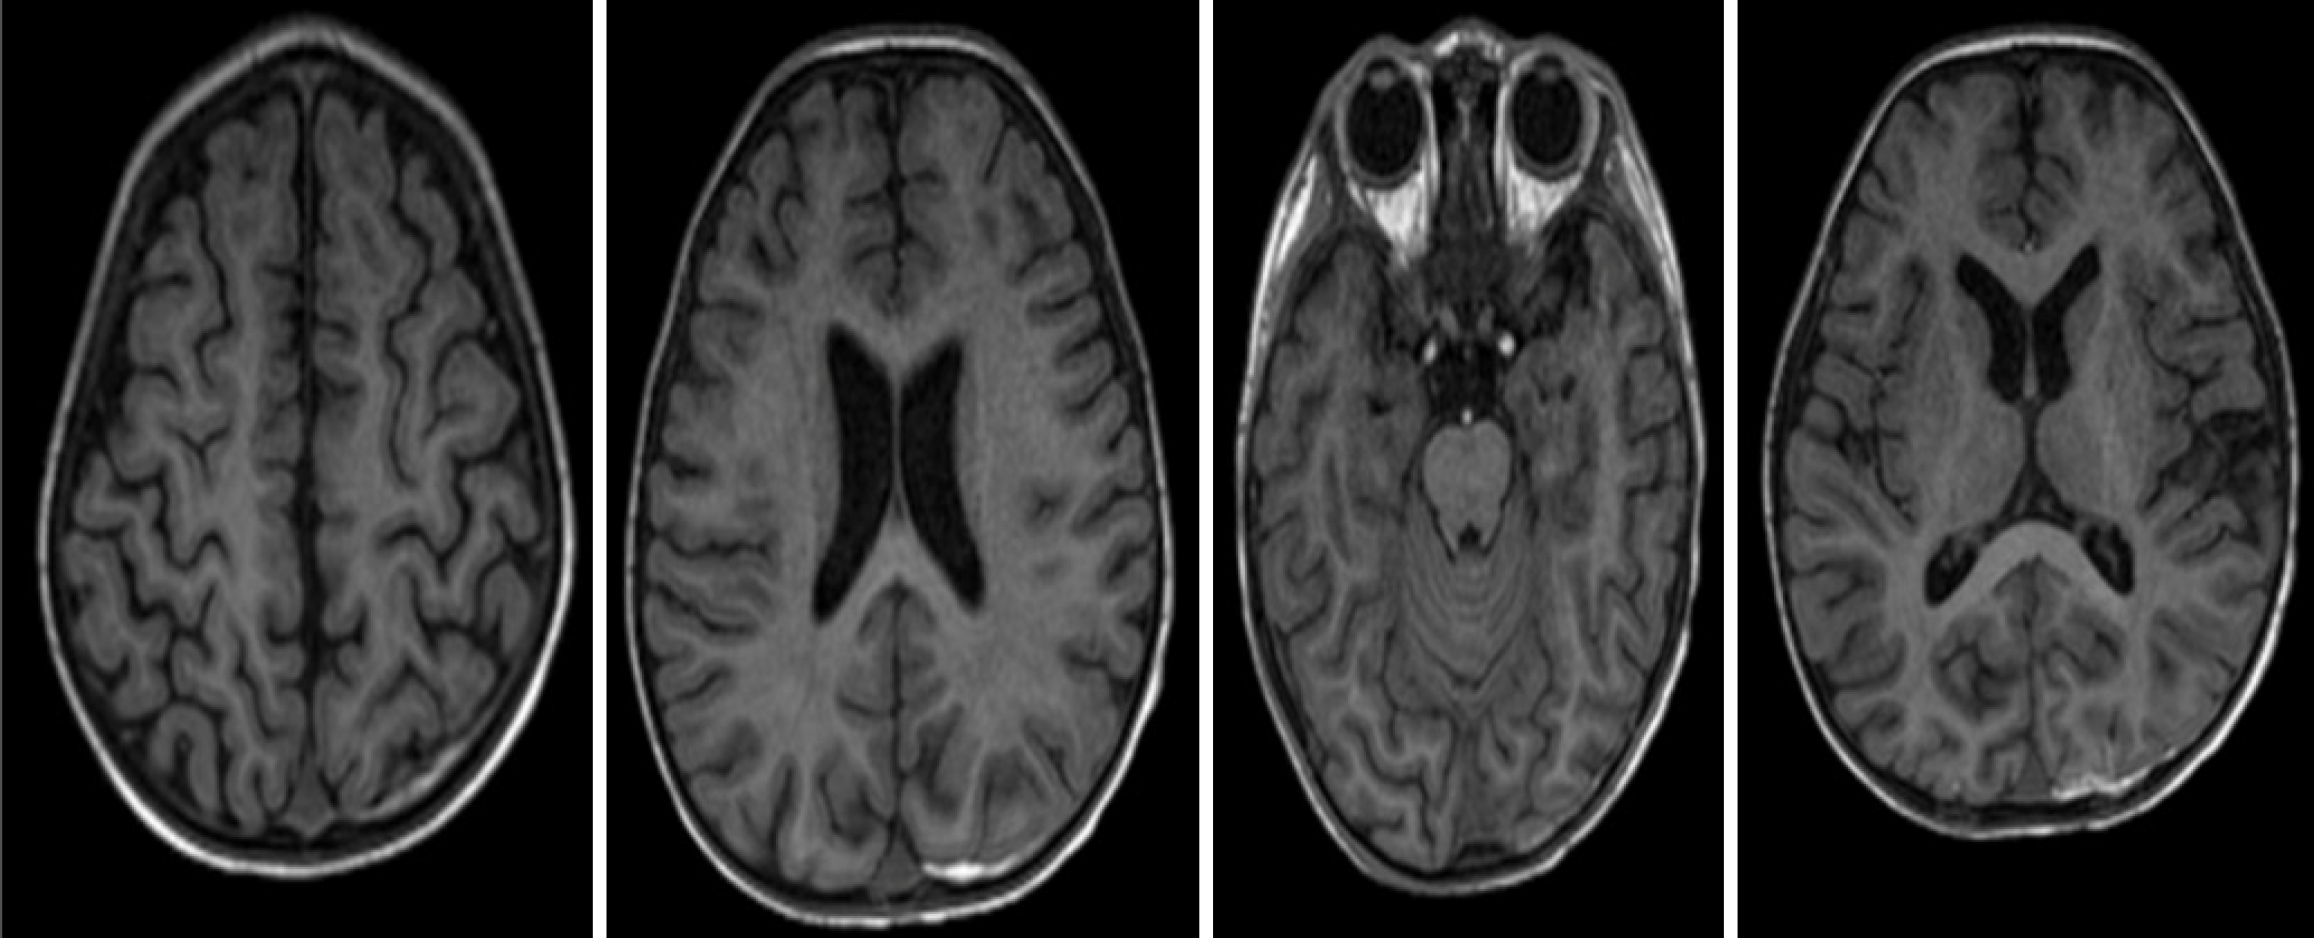

Figure 5 Brain magnetic resonance imaging with contrast showing no evidence of brain injury.